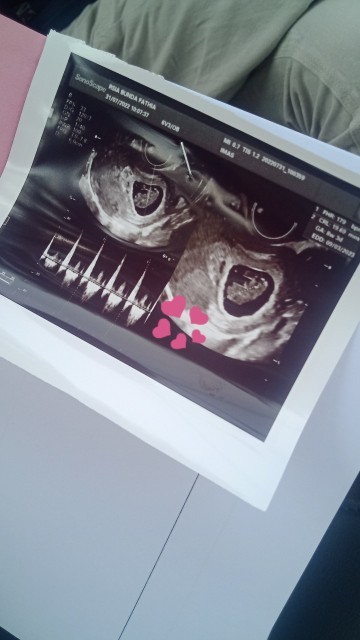

udah Bun waktu usia 5 week hehehe dan pas USG baru tau kalau hamil lagi xixixi